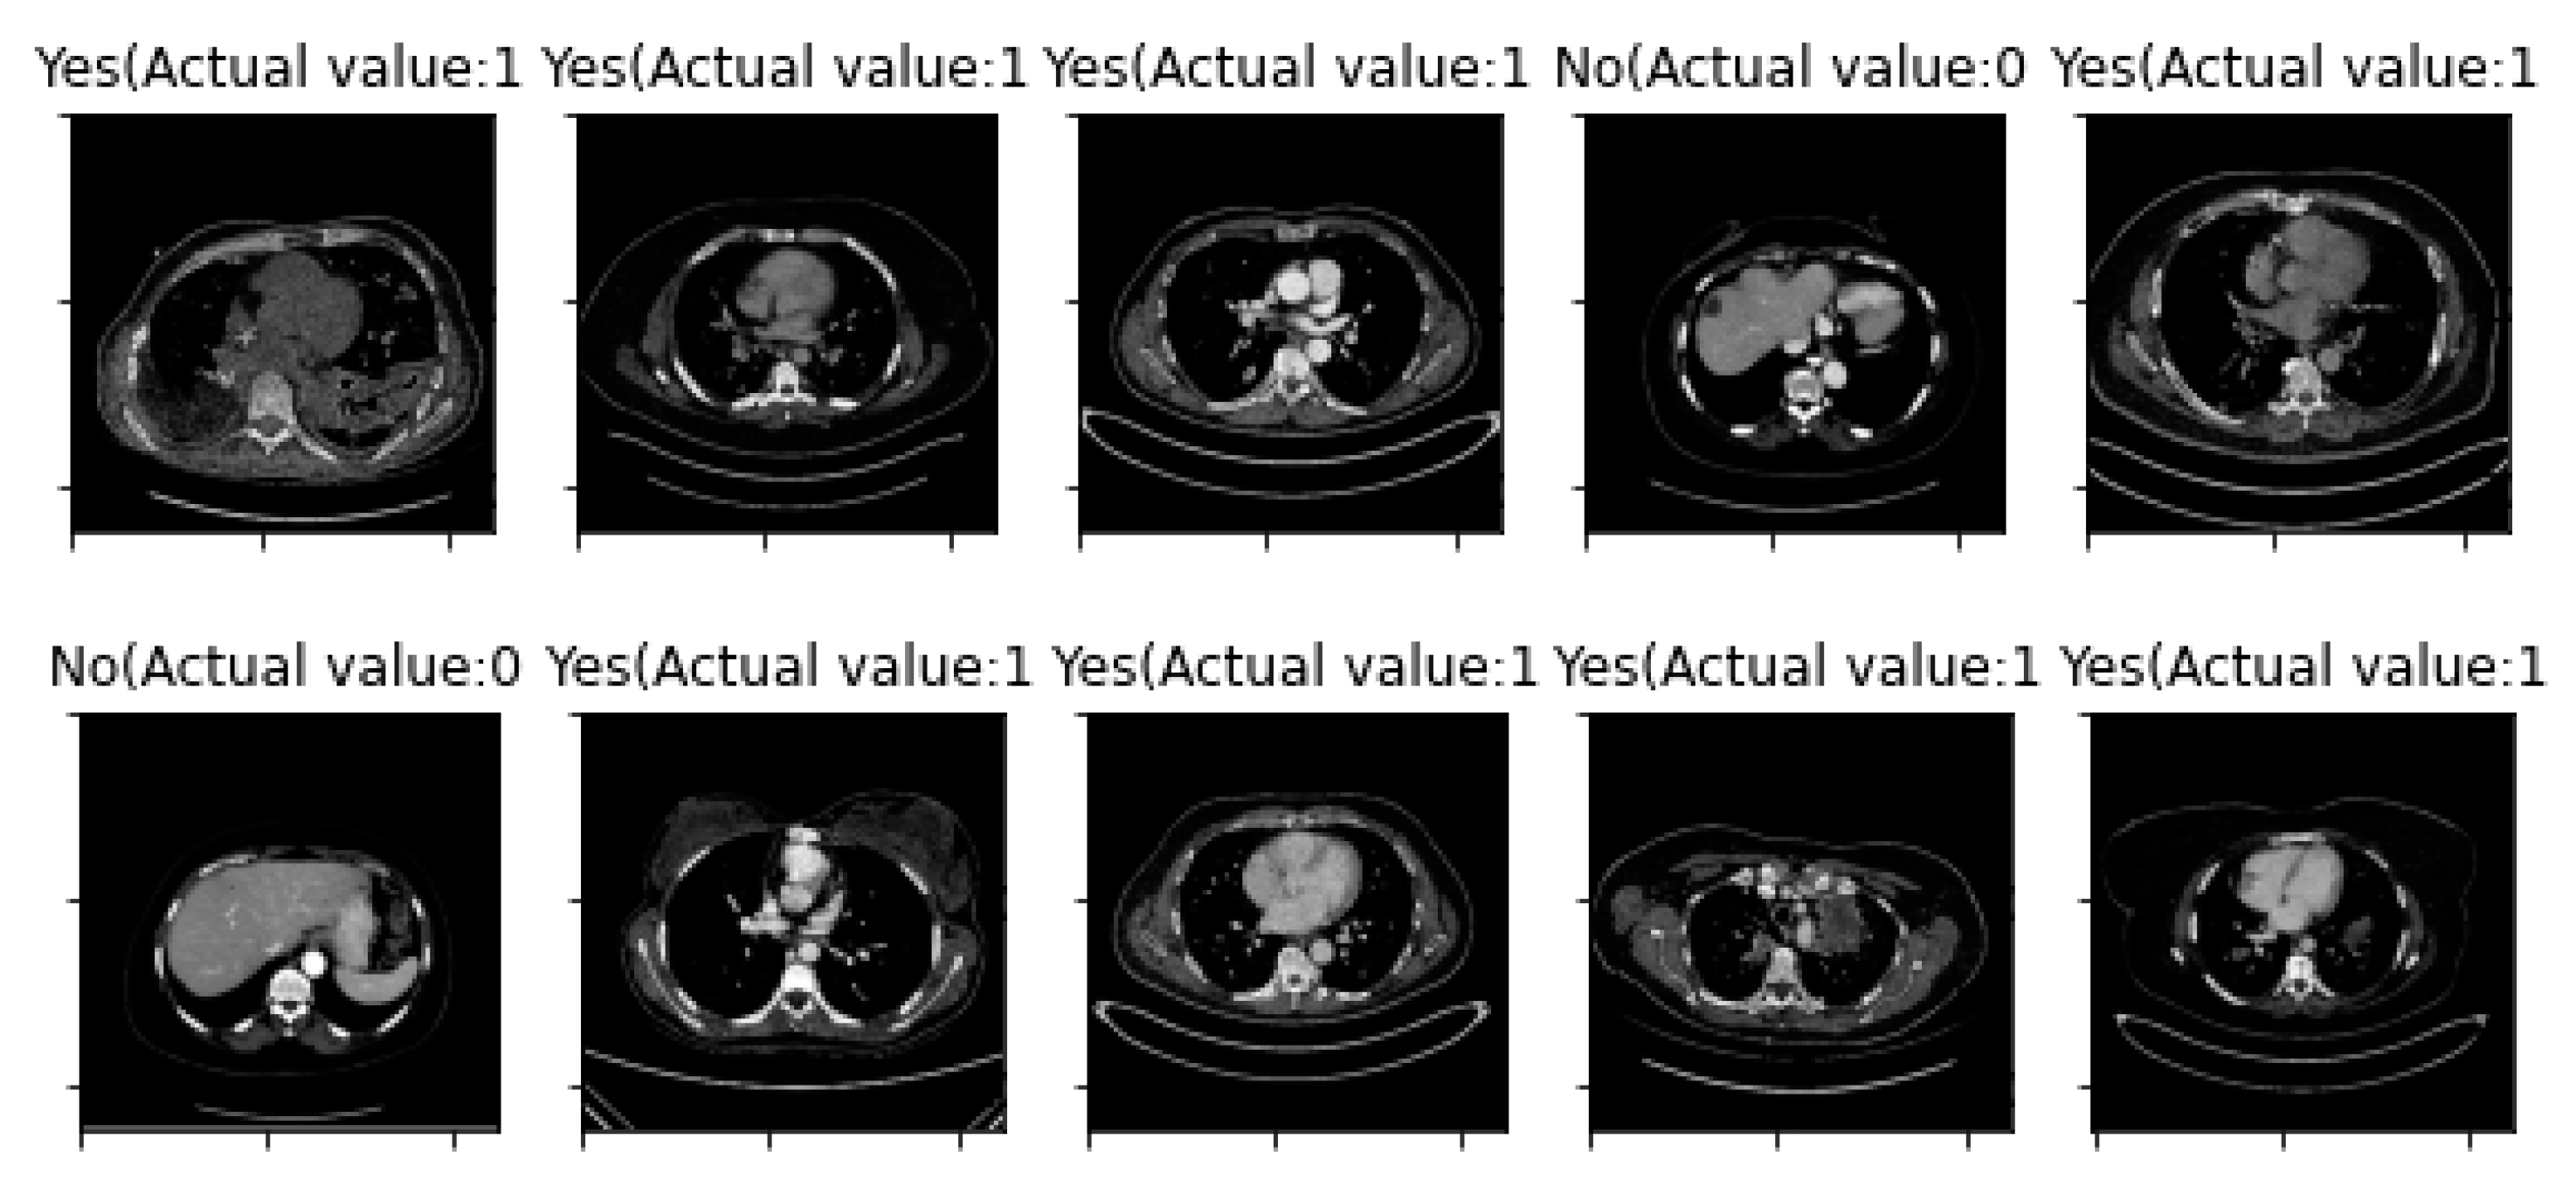

3. Results

| First Run: | Second Run: | ||

| Training Sample Error Rate | 5% | Training Sample Error Rate | 5% |

| Testing Sample Error Rate | 14.586% | Testing Sample Error Rate | 8.091% |

| Accuracy | 85.414% | Accuracy | 91.909% |

| Image Number | Overlaid Image | Deep Lesion Label | CNN Result | Clinical Radiologist’s Diagnosis | Grad-CAM Helpfulness |

|---|---|---|---|---|---|

| 1 | ![]() | Has Tumor | Has Tumor | Has Tumor | Some |

| 2 | ![]() | Has Tumor | Has Tumor | Has Tumor | Yes |

| 3 | ![]() | Has Tumor | Has Tumor | Has Tumor | Yes |

| 4 | ![]() | Has Tumor | Has Tumor | Has Tumor | Yes |

| 5 | ![]() | Has Tumor | Has Tumor | Has Tumor | Yes |

| 6 | ![]() | No Tumor | Has Tumor | Has Tumor | Yes |

| 7 | ![]() | Has Tumor | Has Tumor | Has Tumor | Yes |

| 8 | ![]() | Has Tumor | Has Tumor | Has Tumor | Yes |

| 9 | ![]() | Has Tumor | Has Tumor | Has Tumor | Some |

| 10 | ![]() | Has Tumor | Has Tumor | Has Tumor | Yes |

| 11 | ![]() | Has Tumor | Has Tumor | No Tumor (Cyst) | Some |

| 12 | ![]() | Has Tumor | Has Tumor | Has Tumor | Yes |

| 13 | ![]() | Has Tumor | Has Tumor | No Tumor | Yes |

| 14 | ![]() | Has Tumor | Has Tumor | No Tumor (Inflammation of the Biliary Tract) | Some |

| 15 | ![]() | No Tumor | Has Tumor | No Tumor (Cyst) | Some |

| 16 | ![]() | Has Tumor | Has Tumor | Has Tumor | Yes |